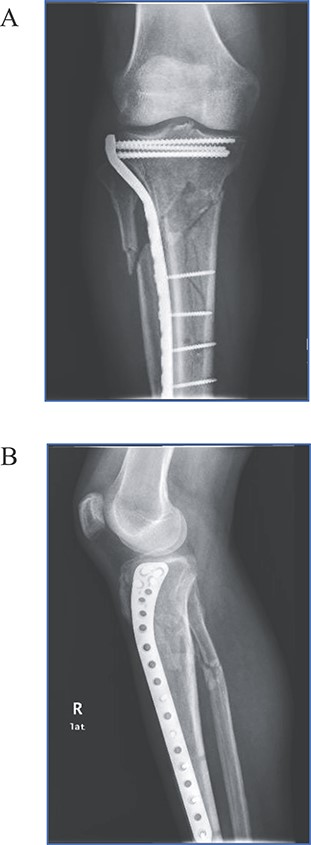

Two-week postoperative follow-up demonstrated a clean wound and intact peripheral pulses. At the 6-week follow-up, clinical evaluation revealed a right mid leg anterolateral pulsating tender mass initially noticed by the patient 8 days prior to this visit. Patient stated no recent trauma. Noninvasive duplex ultrasound performed revealed a 3.4 × 2.7 cm pseudoaneurysm at the ATA (Fig. 3). Patient was referred to endovascular service for recommendations and management. Alternatives such as observation and ultrasound-guided compression or percutaneous ultrasound-guided thrombin injection were discussed with the patient if pseudoaneurysm did not spontaneously thrombose after 1 month. Patient was ultimately managed conservatively since he remained asymptomatic, and latest ultrasound revealed spontaneous resolution by 3 weeks of diagnosis.

Noninvasive duplex ultrasound demonstrating a 3.4 x 2.7 cm pseudoaneurysm at the anterior tibialis artery.